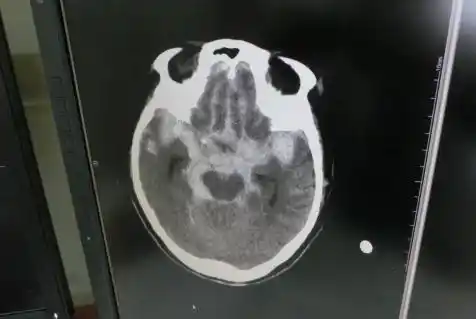

殆ど症状ないSAH、

「ありえないことは一つも無いのが救急」シリーズ: 「こんなSAHでも症状軽いものあり」